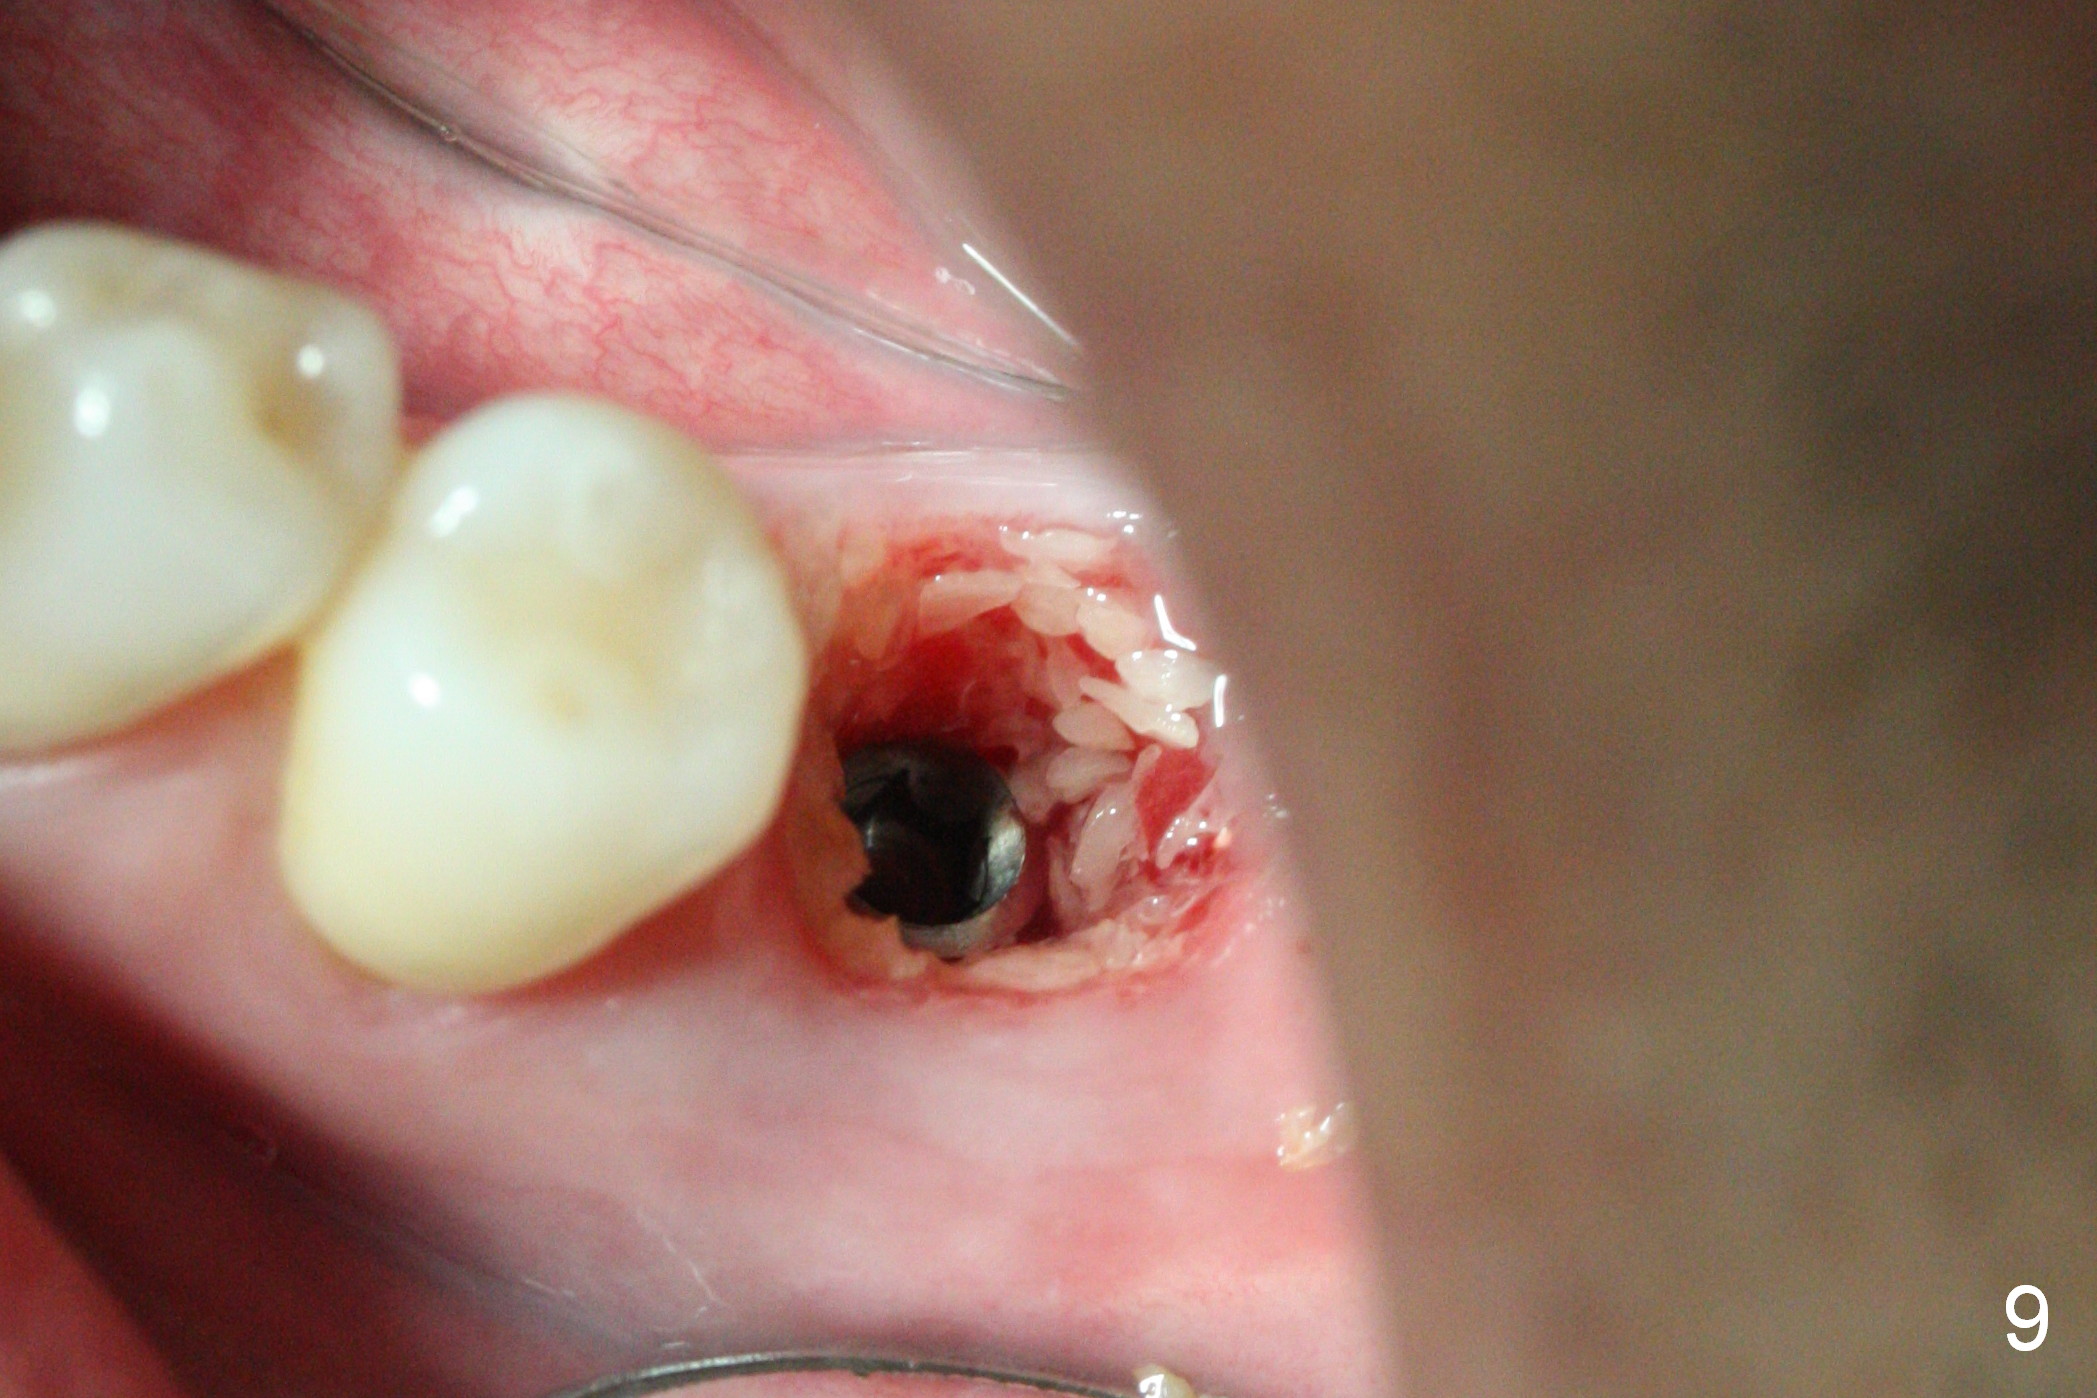

The tooth #19 is easy to get loose, but it cannot be luxated. After sectioning and extraction (Clindamycin), the septum is found to be thin (Fig.4). A surgical fissure bur is used to initiate osteotomy, followed by 1.6 mm pilot drill. It is difficult to use Marking bur (wobbling over the basically pointed septum). It is impossible to use 4.3 mm Magic Drill (MD, one drill system), since it jumps. The smallest MD has to be used (2.8 mm). When the next drill (3.3 mm) is being used for 13 mm with stopper (Fig.5), the patient experiences transient pain. The depth is suggested from the design in Fig.2. The thin septum appears not to be a reliable landmark. When block anesthesia is administered, the initial depth should be shortened. The drill appears to be close to the Inferior Alveolar Canal (Fig.5). Then the depth changes to 11 mm with the following drills (3.8 and 4.3). The mesial and distal walls of the septum are gradually perforated. A 5x9 mm dummy implant is placed only after using 4.8 mm drill (Fig.6). The implant appears to be short. When a longer implant is placed (5x11 mm), it does not easily enter the osteotomy, either sliding into the mesial or distal socket with the implant separating from the implant driver. It appears that a premount implant is appropriate in this situation. When the 5x11 mm implant is finally seated with stability, it is 6 mm apical to the gingival margin. The longest cuff of IBS abutment is 4 mm. A longer implant is needed (Fig.7, 5x13 mm). Placement is not easy as mentioned above. Insertion torque is <20 Ncm when the patient experience a little discomfort. A 6.5x4(4) mm pair abutment is placed (A), apparently proper for restoration. Allograft is placed (Fig.8 *) prior to immediate provisional. The patient complains of bad smell from the site 24 days postop. When the provisional is removed, the abutment is found to be mobile. When the latter is removed with local anesthesia, bone graft granules are attached to the socket above the lightly mobile implant (Fig.9). In fact the latter appears to be stable after a few turns by finger. A healing screw is placed; the socket is closed with collagen plug and 4-0 Chromic gut sutures (Fig.10). It appears that a larger implant should have been used to achieve higher torque. Two months later (3 months postop), the coronal end of the implant is partially exposed. A 5x4 mm healing abutment is placed. It appears that the implant is stable. The implant appears to have osteointegrated 4 months postop (Fig.11). Impression is taken.